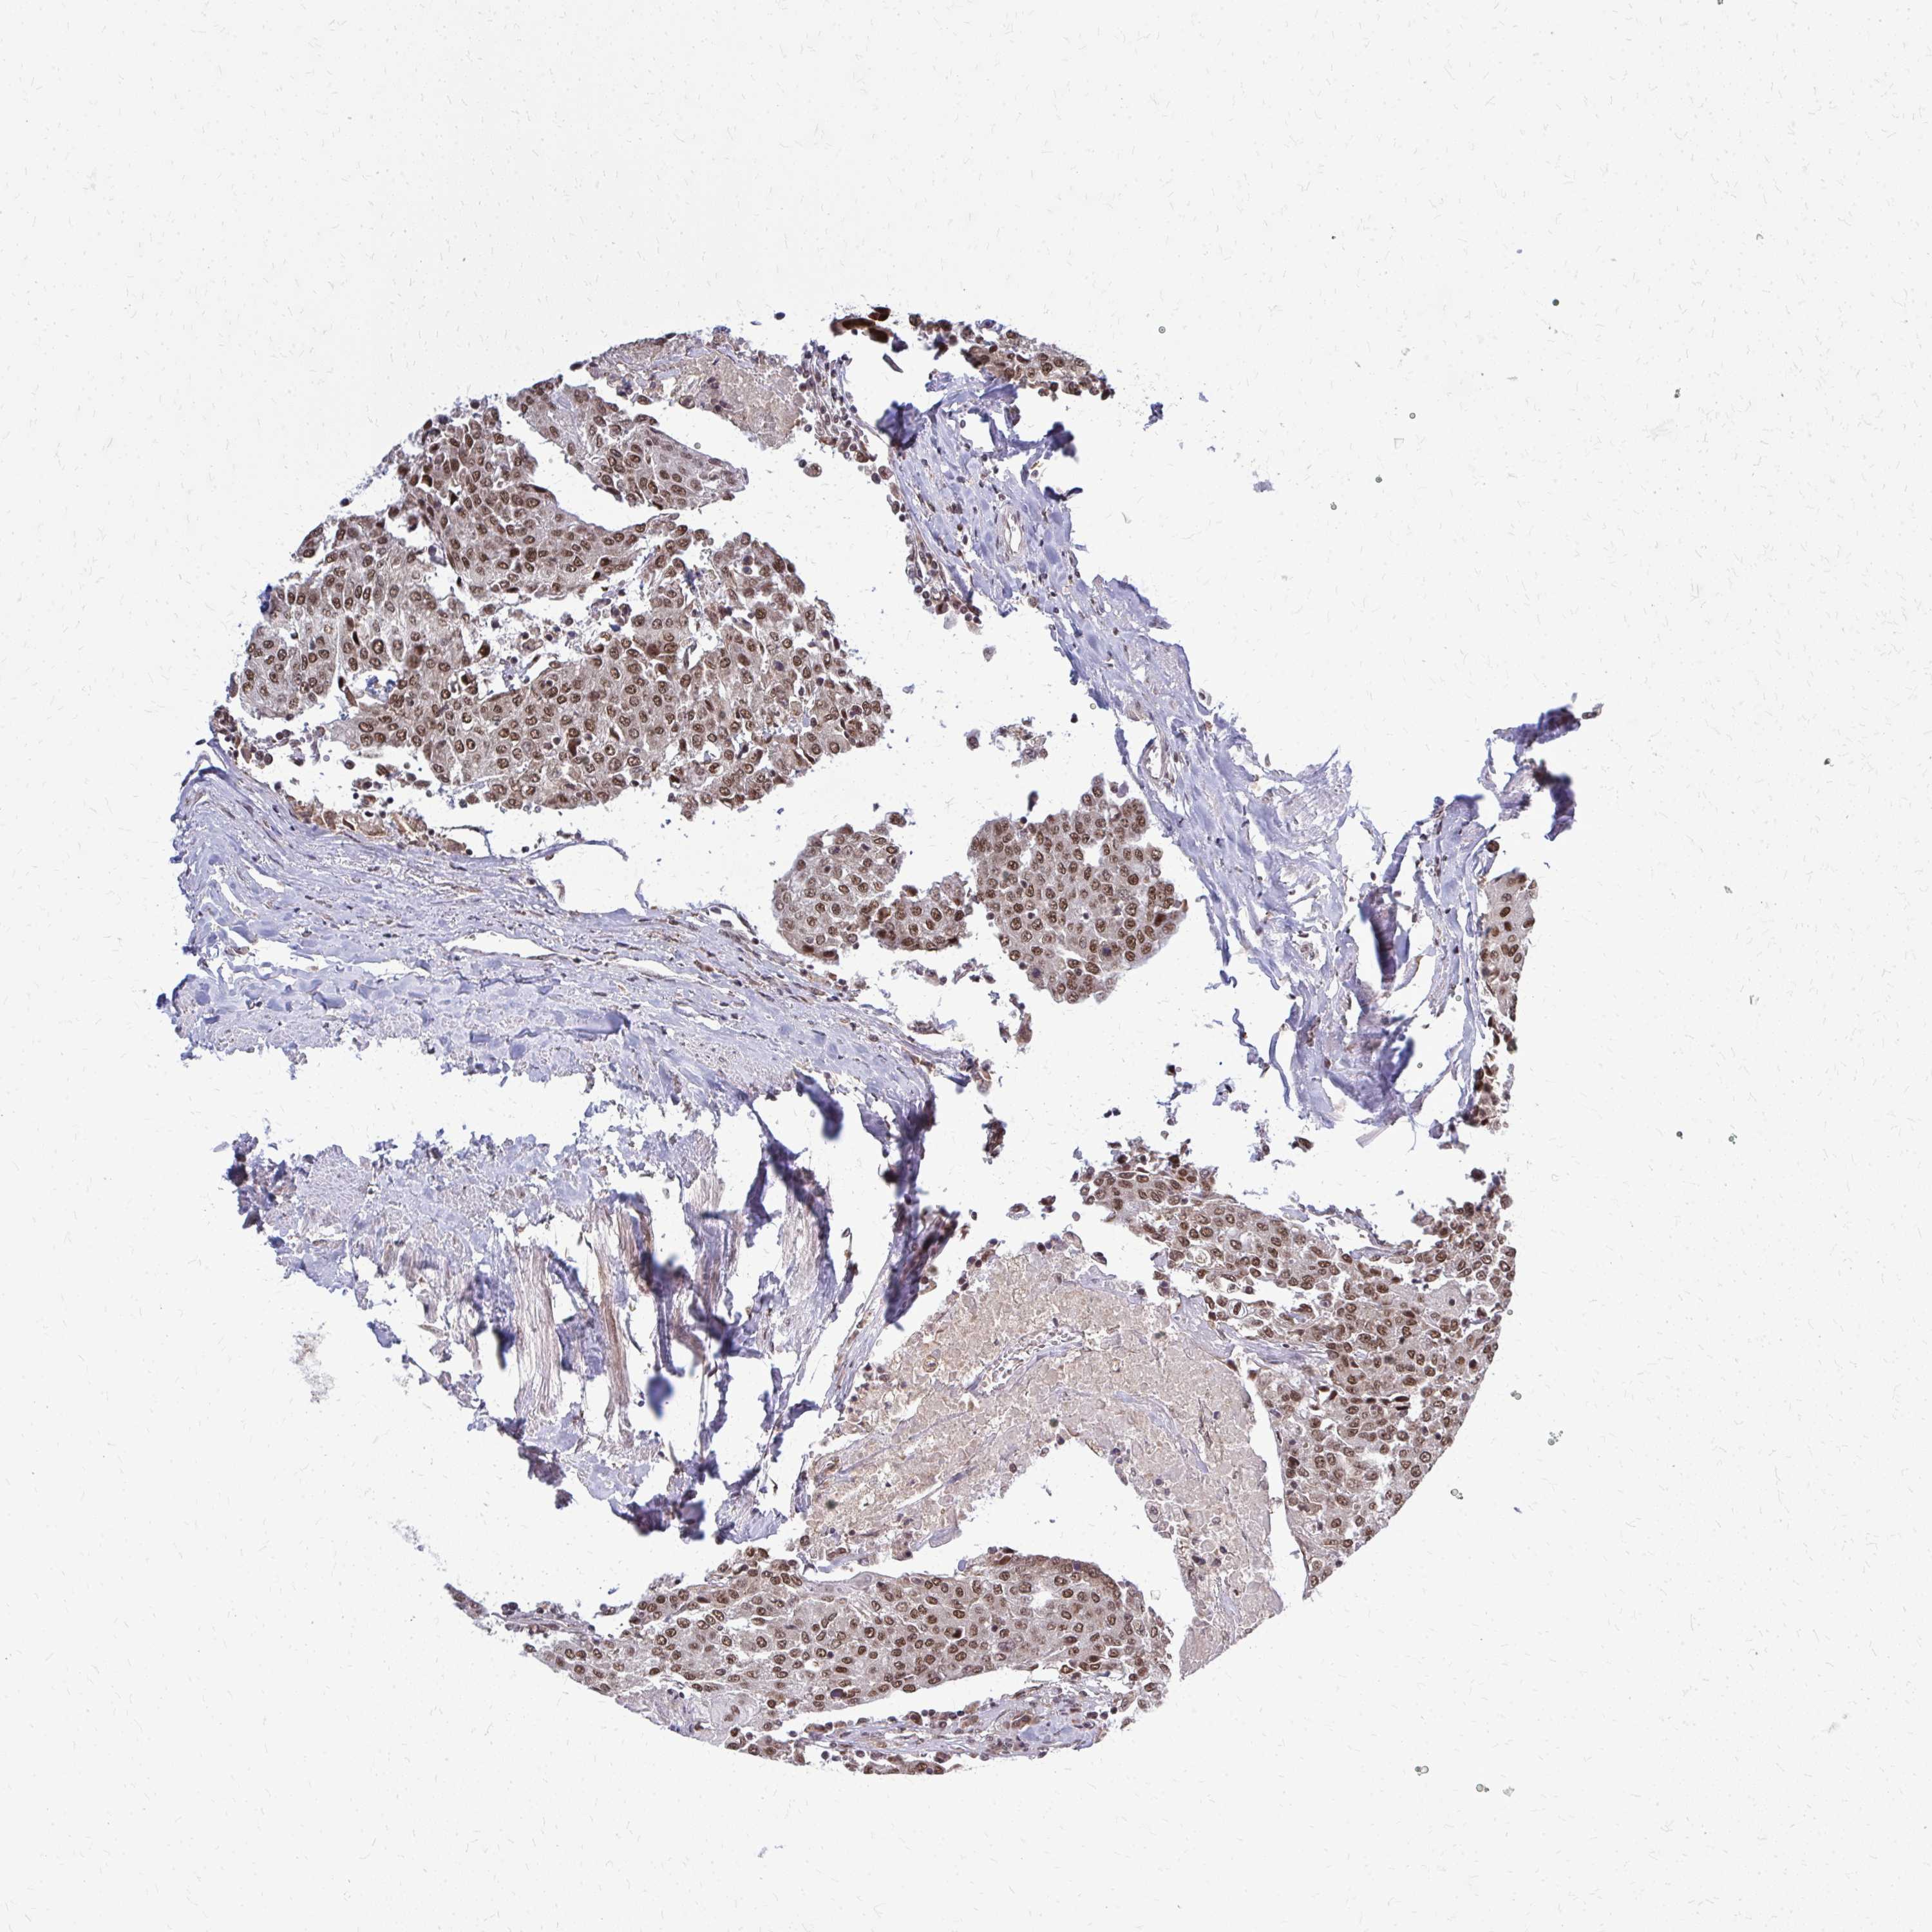

UROTHELIAL CANCER - Protein expressioni

A mouse-over function shows sample information and annotation data. Click on an image to view it in a full screen mode. Samples can be filtered based on level of antibody staining by selecting one or several of the following categories: high, medium, low and not detected. The assay and annotation is described here.

Note that samples used for immunohistochemistry by the Human Protein Atlas do not correspond to samples in the TCGA dataset.

Antibody stainingi

Antibody staining in the annotated cell types in the current human tissue is reported as not detected, low, medium, or high, based on conventional immunohistochemistry profiling in selected tissues. This score is based on the combination of the staining intensity and fraction of stained cells.

Each image is clickable and will lead to virtual microscopy that enables deeper exploration of all samples and also displays staining intensity scores, fraction scores and subcellular localization as well as patient and tissue information for each sample.

Antibody HPA052052

Antibody CAB005583

Antibody CAB072336

Staining

High

Medium

Low

Not detected

Intensity

Strong

Moderate

Weak

Negative

Quantity

>75%

75%-25%

<25%

None

Location

Nuclear

Cytoplasmic/membranous

Cytoplasmic/membranous,nuclear

Urothelial carcinoma, High grade

Urothelial carcinoma, Low grade

Urothelial carcinoma, NOS